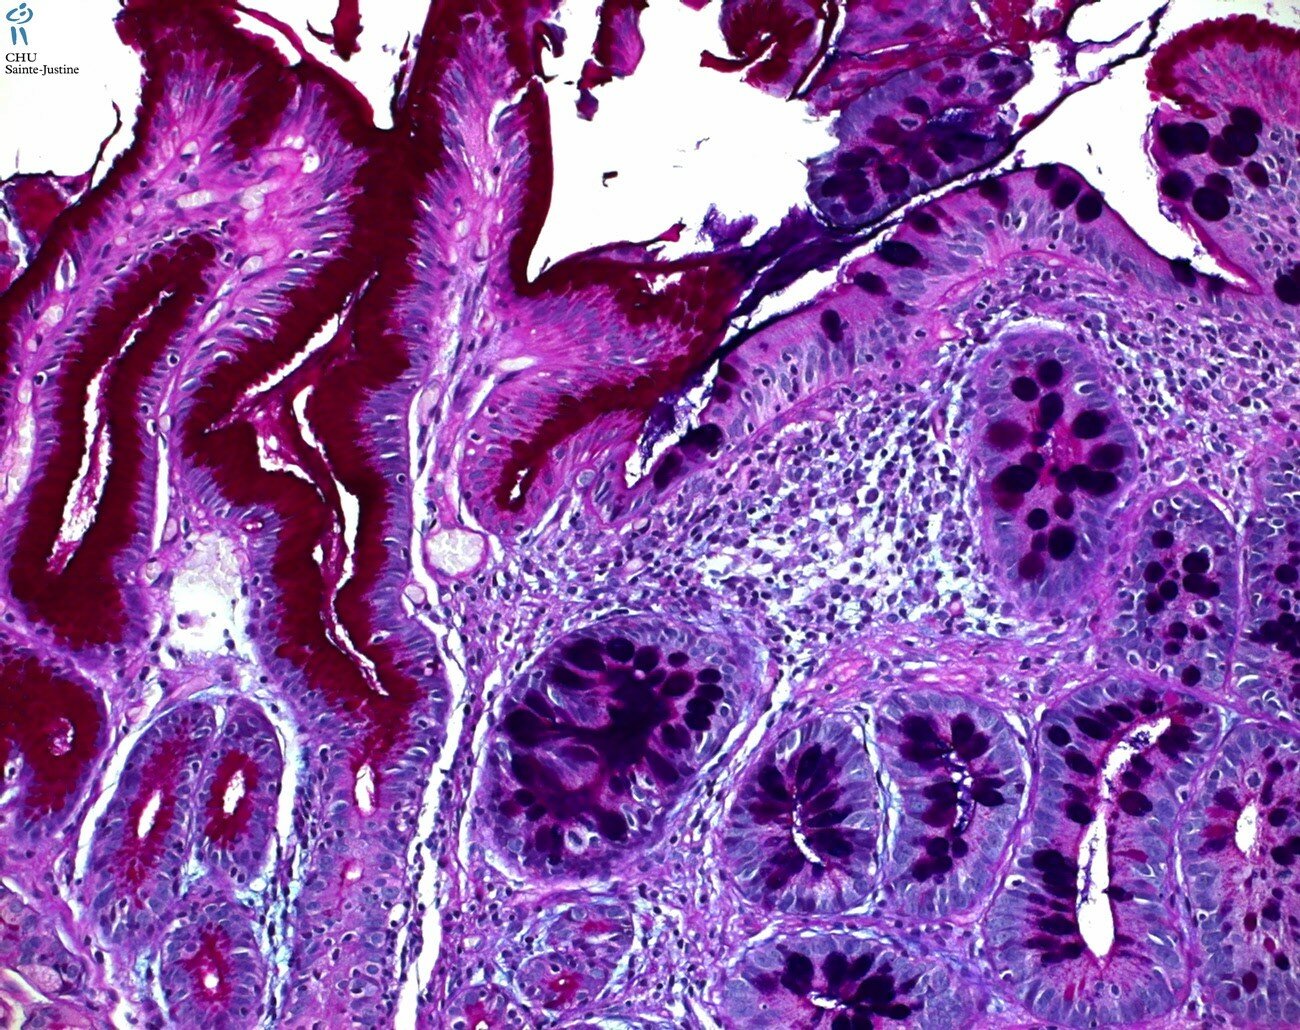

intestinal metaplasia in stomach